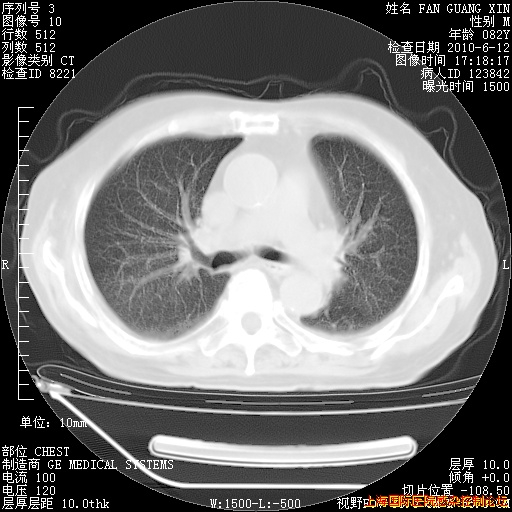

补发6月12日肺部CT肺窗

6月12日肺窗

整整相隔30天的肺部CT好像有所好转啊。甲强龙减量第3天,需要观察体温。